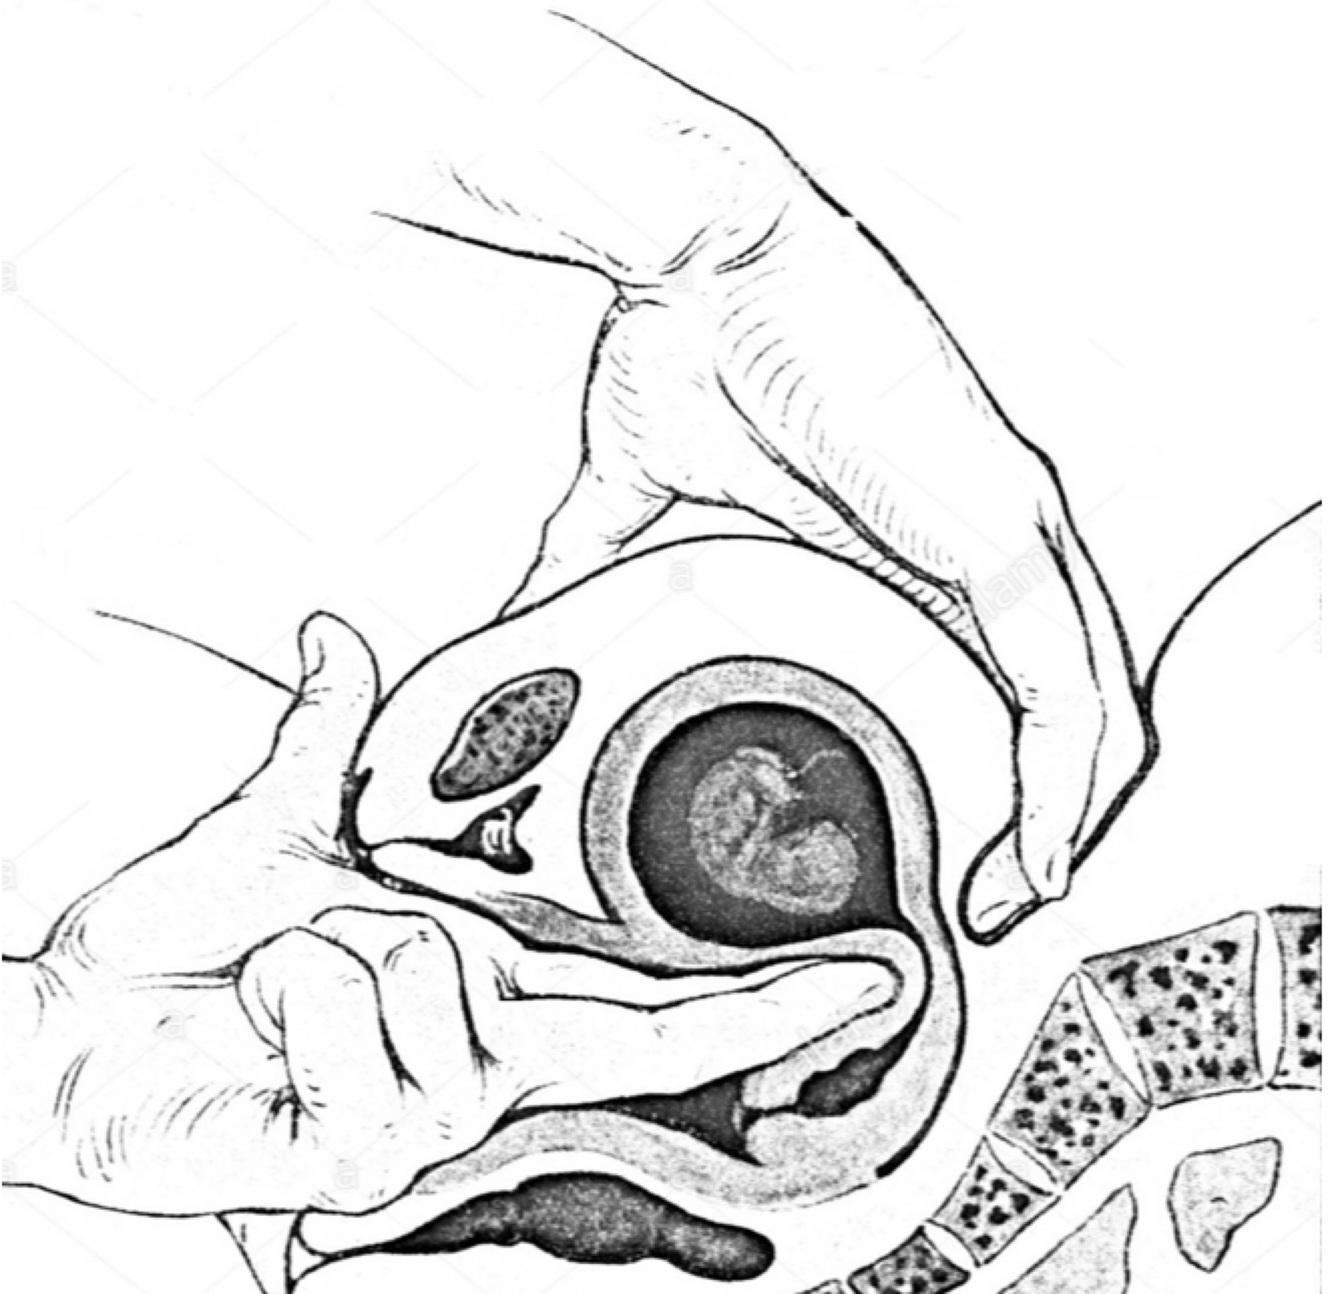

Sinal de Puzos

O que é? Como avaliar? Presente a partir de qual IG?